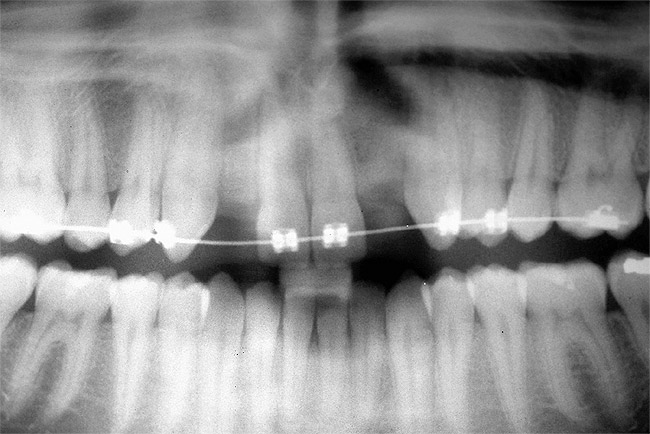

Periapical radiographs were taken to help determine the mesial-distal inclinations of the adjacent tooth roots (Figure 1). The radiographs revealed a serious issue, convergent roots for the right canine and right central, which eliminated that area as a potential implant-receptor site. The space between the left central and canine teeth was minimal, although the roots were relatively parallel. Clinical examination (manual palpation of the root eminences superiorly to the vestibule on the right side) confirmed the root convergence (Figure 2A). The flat, wide zone of the keratinized tissue and lack of interdental papilla was evident for the missing right lateral incisor. There was a marked difference in clinical appearance for the left lateral, which could impact the eventual plan of treatment (Figure 2B). Other significant clinical findings included bilateral facial bone concavities, which existed as a result of the congenitally missing tooth roots. As a diagnostic cue to the underlying bone topography, it is important to follow the demarcation between attached and unattached gingival tissue, and note the crestal width of the available keratinized tissue (Figure 2C).

Figure 1  Pretreatment radiographs revealed convergent roots for the right canine and right central.

Figure 1